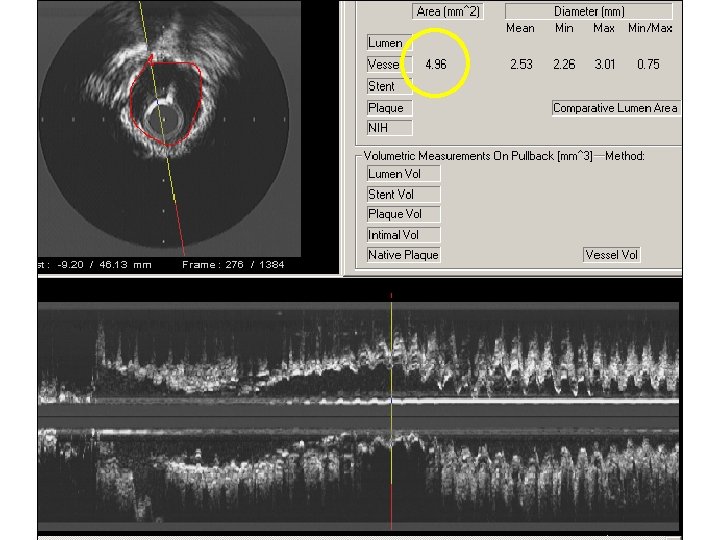

IVUS: Unexpanded Stent due to Concentric Calcification

A fully expanded balloon on angiography does not insure that the lesion/stent is fully expanded

Unexpanded Stent 3. 0 balloon at 28 atm

A Fully Expanded Balloon does not insure the Lesion has Expanded 3. 0 mm Quantum at 28 atm

IVUS after Quantum at 28 atm.